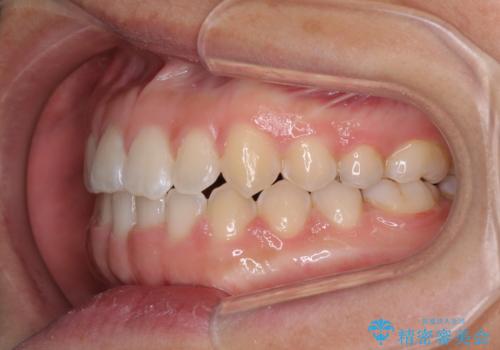

前歯の隙間を閉じたい 短期間でのワイヤー矯正

元々の歯並びが悪くなかったため、9ヶ月で綺麗に仕上がりました。

すきっ歯は後戻りを起こしやすいため、上下ともに歯の裏側を細いワイヤーで固定した上で、リテーナーのマウスピースを装着していただいています。